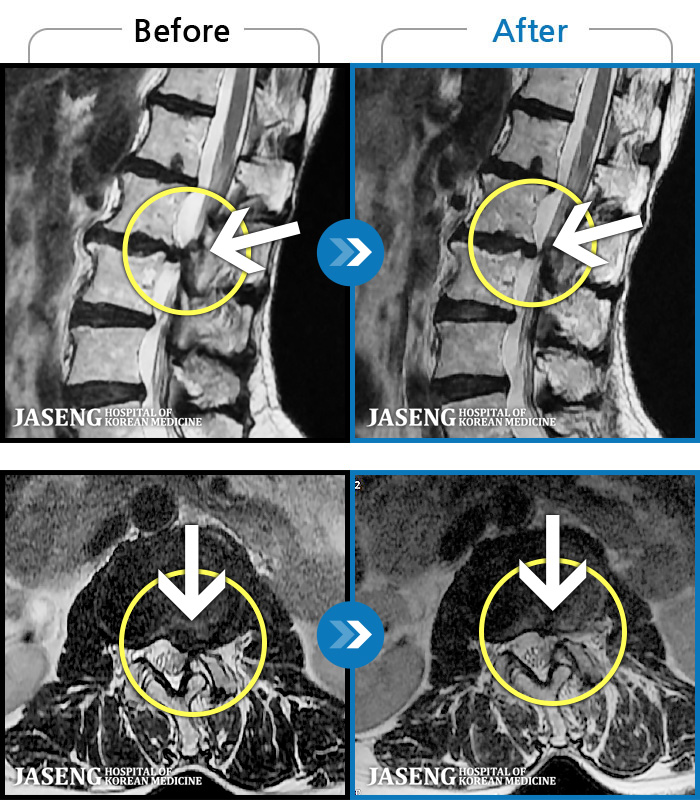

허리디스크

해운대 · 김상돈 원장

아래쪽 허리와 우측 골반에 통증이 있었습니다.

촬영시기

2019.08.26 ~ 2025.08.09

2025.08.14

조회수 262